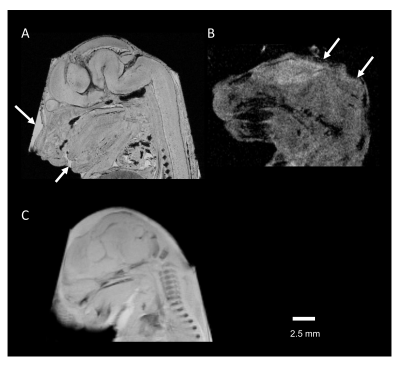

Figure 3 (A) Retained water on the surface of the tissue shows a high-signal intensity (arrow). (B) Susceptibility artifact caused by air bubbles on tissue-air interfaces at the tissue edges (arrow). (C) The blurred edge of the image is caused by tissue movements. These images were obtained using FC43 surrounding the embryo tissue.